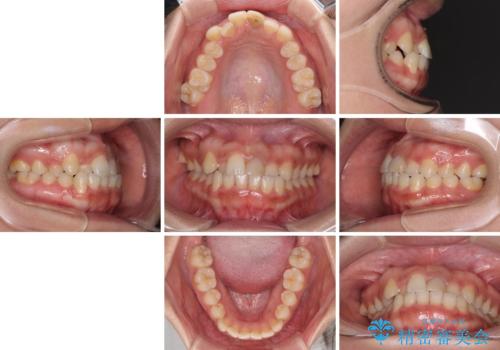

前歯のクロスバイトと変色した歯 ワイヤー矯正とセラミック治療

- 前歯のクロスバイトと神経を取り除いた後に変色してしまった前歯を気にして来院された患者様です。

ワイヤー矯正により矯正治療を行った後に、前歯の補綴治療を行うこととしました。

変色してしまった前歯は、反対側の歯と比べて歯肉が覆い被さっていたため、骨整形を含めた歯周外科処置を行い、歯肉ラインを整えることとしました。